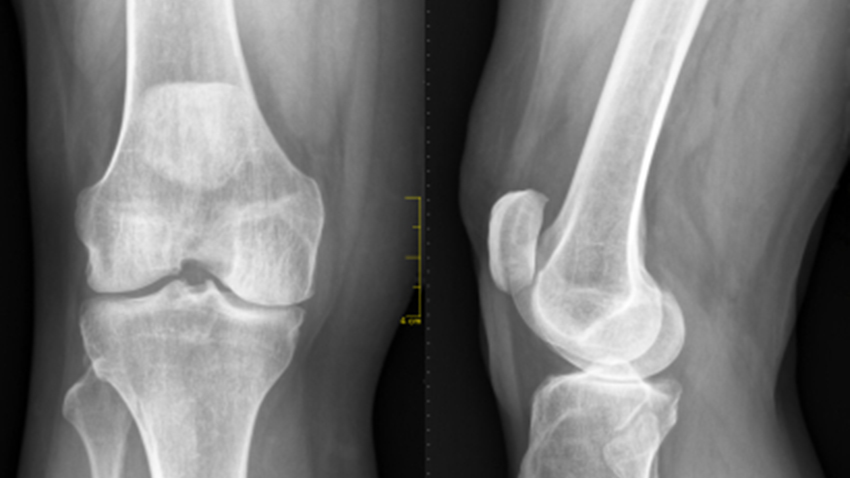

Osteomalacia

Osteomalacia refers to a marked softening of your bones, most often caused by severe vitamin D deficiency. The softened bones of children and young adults with osteomalacia can lead to bowing during growth, especially in weight-bearing bones of the legs. Osteomalacia in older adults can lead to fractures.